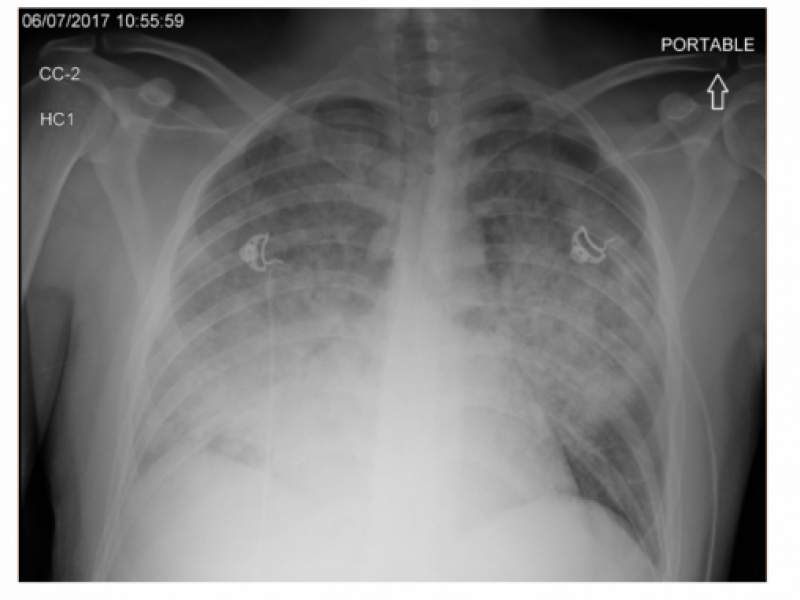

A 42-year-old male with past medical history of hypertension